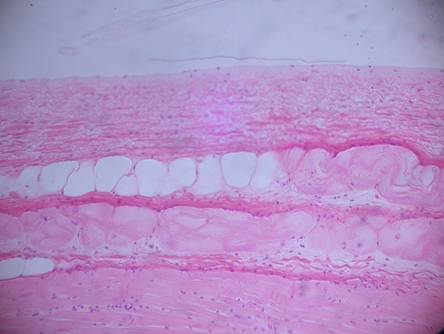

Фото 1.5.1. Стенка сердца. Эндокард и миокард.

Гем.-Эоз. Малое увеличение. (Ув.10х7)

| сократительные кардиомиоциты (поперечный срез) | |

| сократительные кардиомиоциты (продольный срез) | |

Фото 1.5.7. Эндокард быка. Гем.-Эоз.

Среднее увеличение. (Ув.10х7)

| сократительные кардиомиоциты | |

| гладкие миоциты мышечно-эластического слоя | |